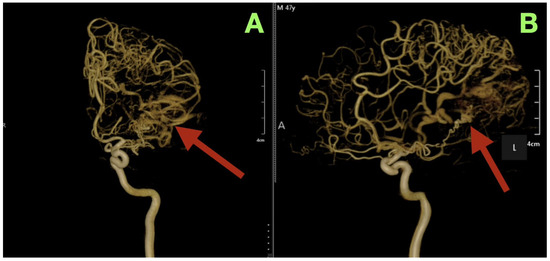

Background/Objectives: Arteriovenous malformations (AVMs) in the dominant temporo-parieto-occipital (TPO) junction of the brain are extremely rare and very difficult to remove surgically because this area includes multiple sensory and language networks. Due to the fact that many patients present with bleeding, surgeons have to find a delicate balance between removing all of the AVM tissue and preserving the functional areas of the brain where important functions occur. This study is reporting a case demonstrating how precise clinical–radiologic correlation, detailed anatomical knowledge, and deliberate microsurgical techniques can allow safe removal of the AVM and improve the patient’s neurologic function without the need for additional intraoperative technology. Case Presentation: A 47-year-old right-handed male patient experienced persistent neurological deficits after experiencing a hemorrhage from an AVM in his dominant posterior hemisphere, which included mild language difficulties, right hemifacial–brachial spasticity, parietal sensory loss and a visual field defect of his right eye known as an inferior quadrantanopia localized to the TPO junction. Cerebral angiography identified a small, compact, high-flow AVM (40 × 30 mm) fed by distal branches of the middle cerebral artery (M4), posterior cerebral artery (P4), anterior cerebral artery (A4), as well as a small branch of the superior cerebellar artery (SCA). Blood drained into two veins of the Trolard and Labbé. The authors removed the AVM completely by circumferential dissection of the nidus along gliotic planes using a microscope. Feeders were then sequentially disconnected, and the venous outflow was preserved until the AVM could be removed en bloc. Post-operative angiograms demonstrated complete removal of the AVM with normalization of blood flow to the surrounding cortex. The patient’s neurologic function improved over time and at three months post-operatively, he was functioning independently (modified Rankin Scale = 1; Barthel Index = 100) and there was no evidence of residual nidus or edema on imaging. Conclusions: High-flow AVMs in the dominant TPO junction can be completely removed using a disciplined microsurgical approach and a feeder first/vein last disconnection method based on anatomy. The patient’s improvement in function represented reperfusion and reintegration of an injured but still functional network of the brain, reinforcing the idea that careful observation, a deep understanding of brain anatomy, and restrained surgical technique are critical to achieving long-term results in AVM surgery. Full article

Figure 1